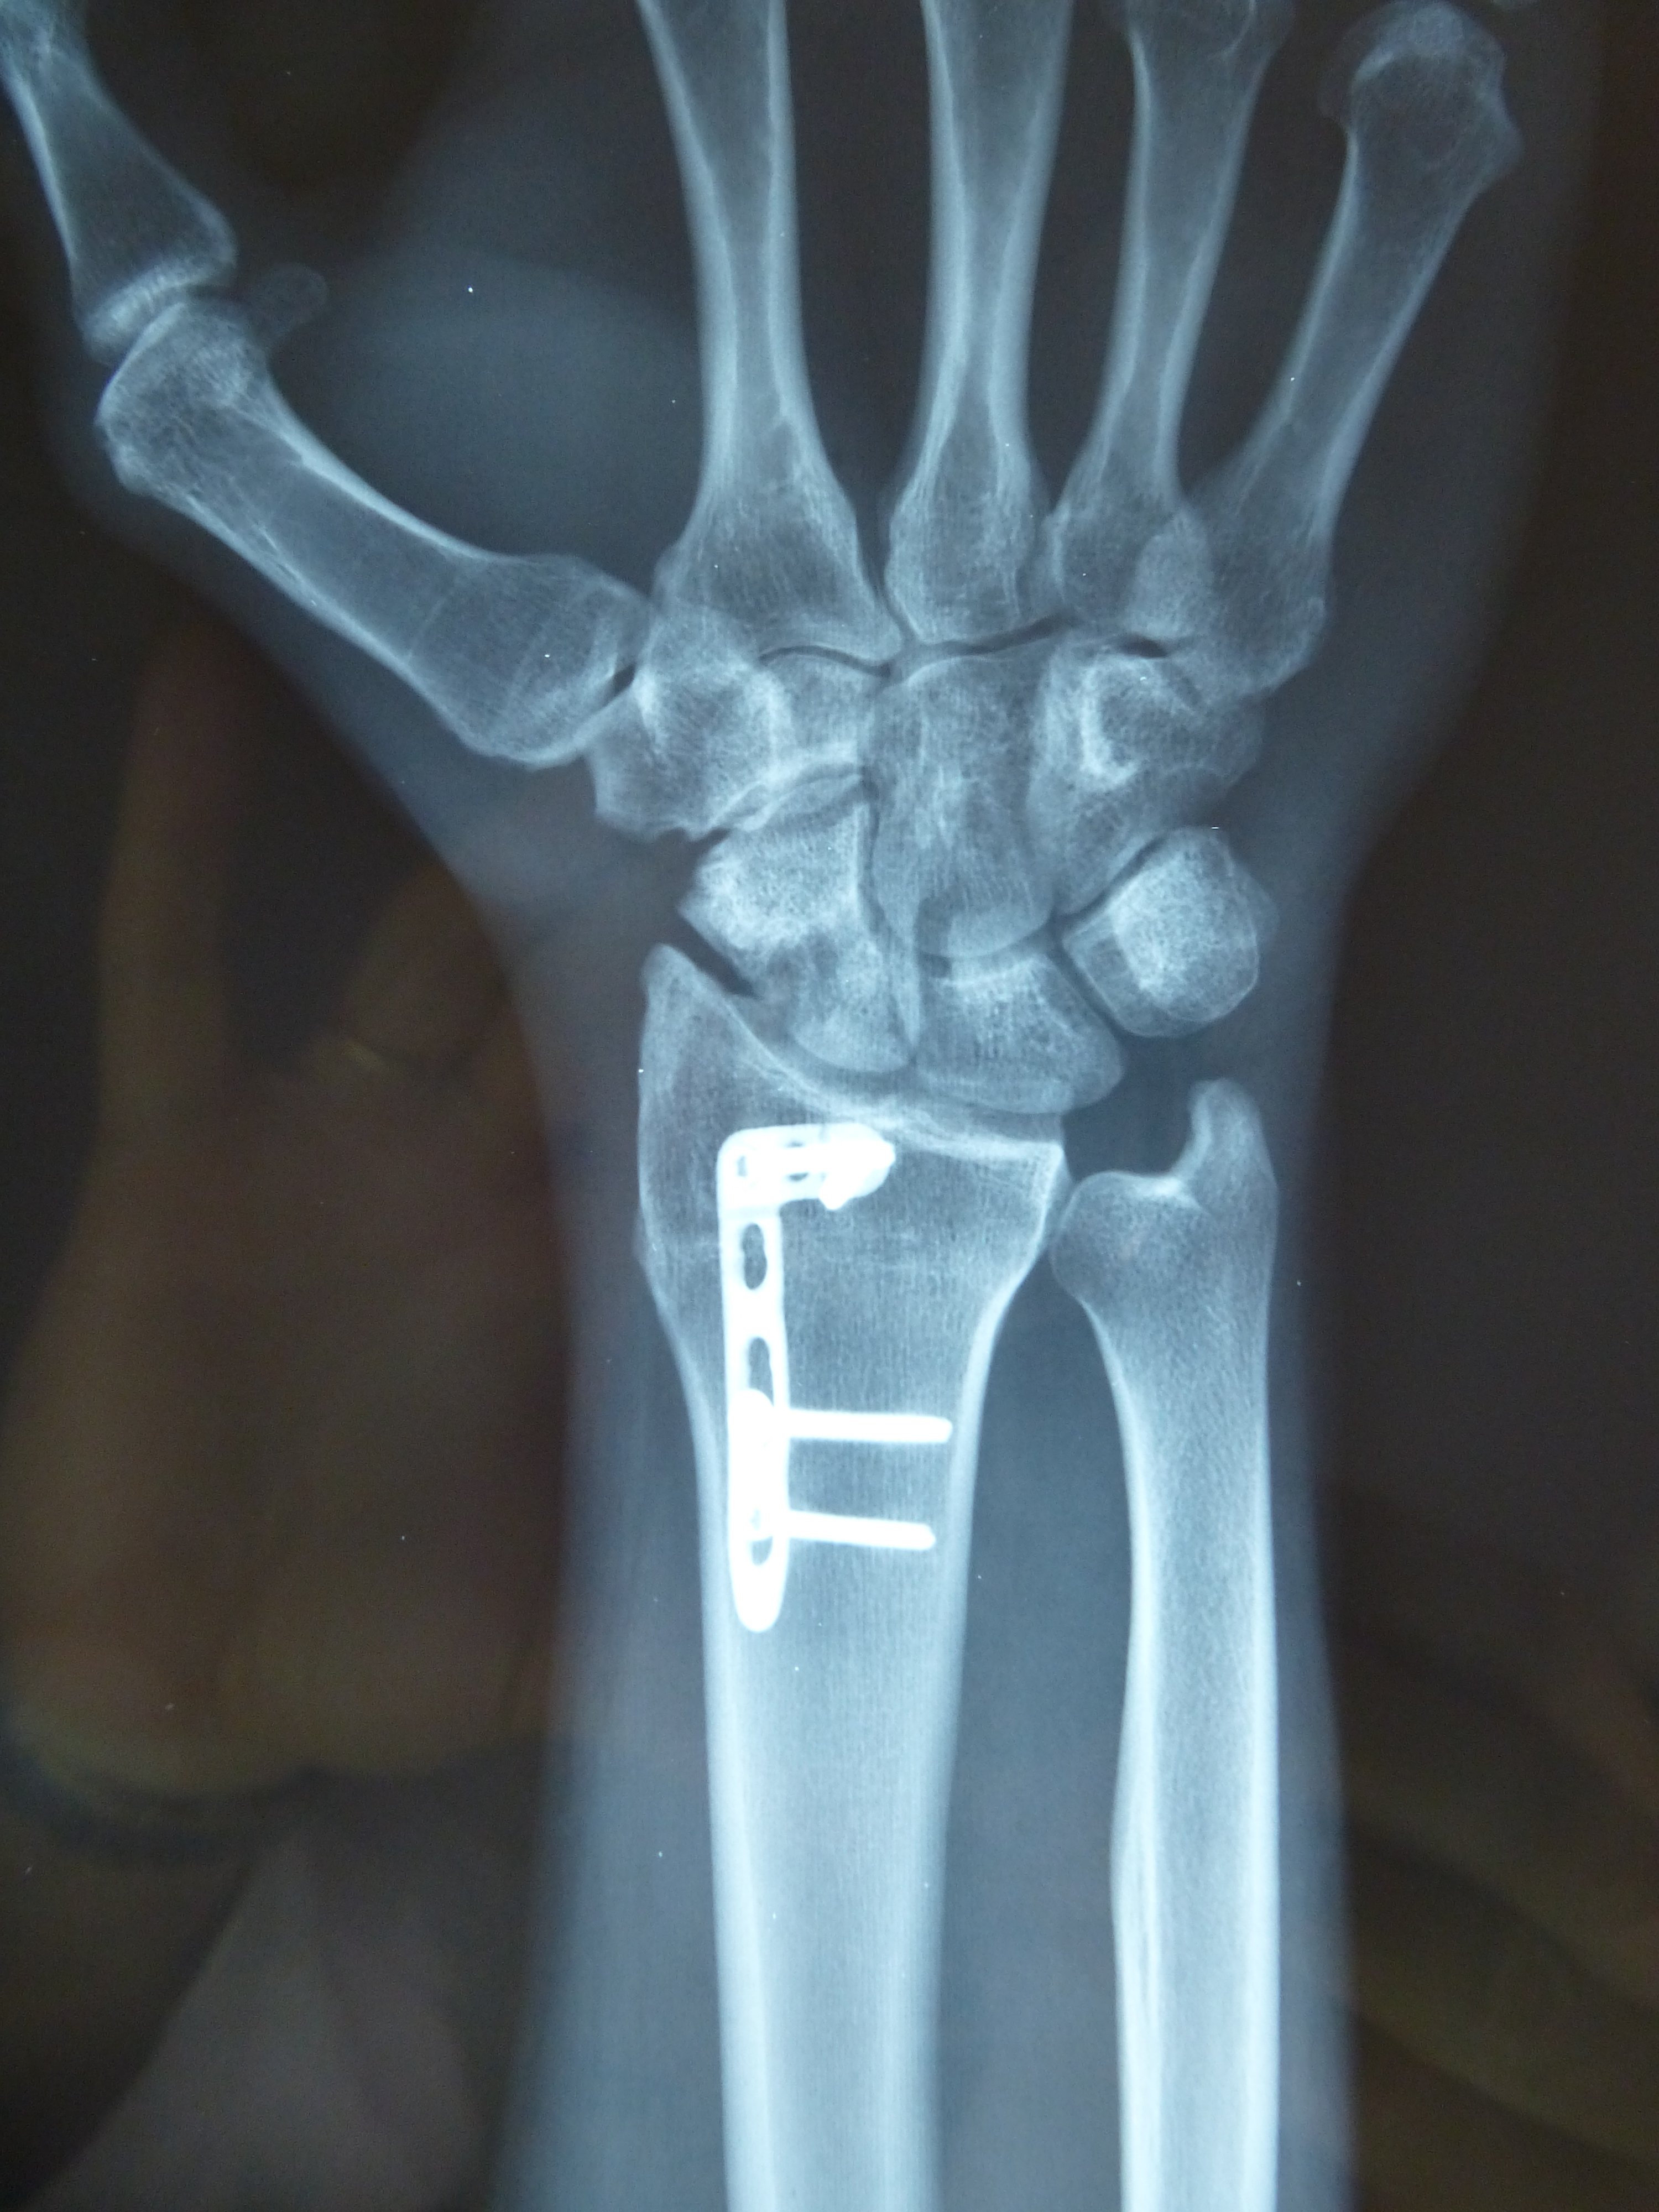

Προεγχειρητικά

Μετεγχειρητικά 1

Μετεγχειρητικά 2